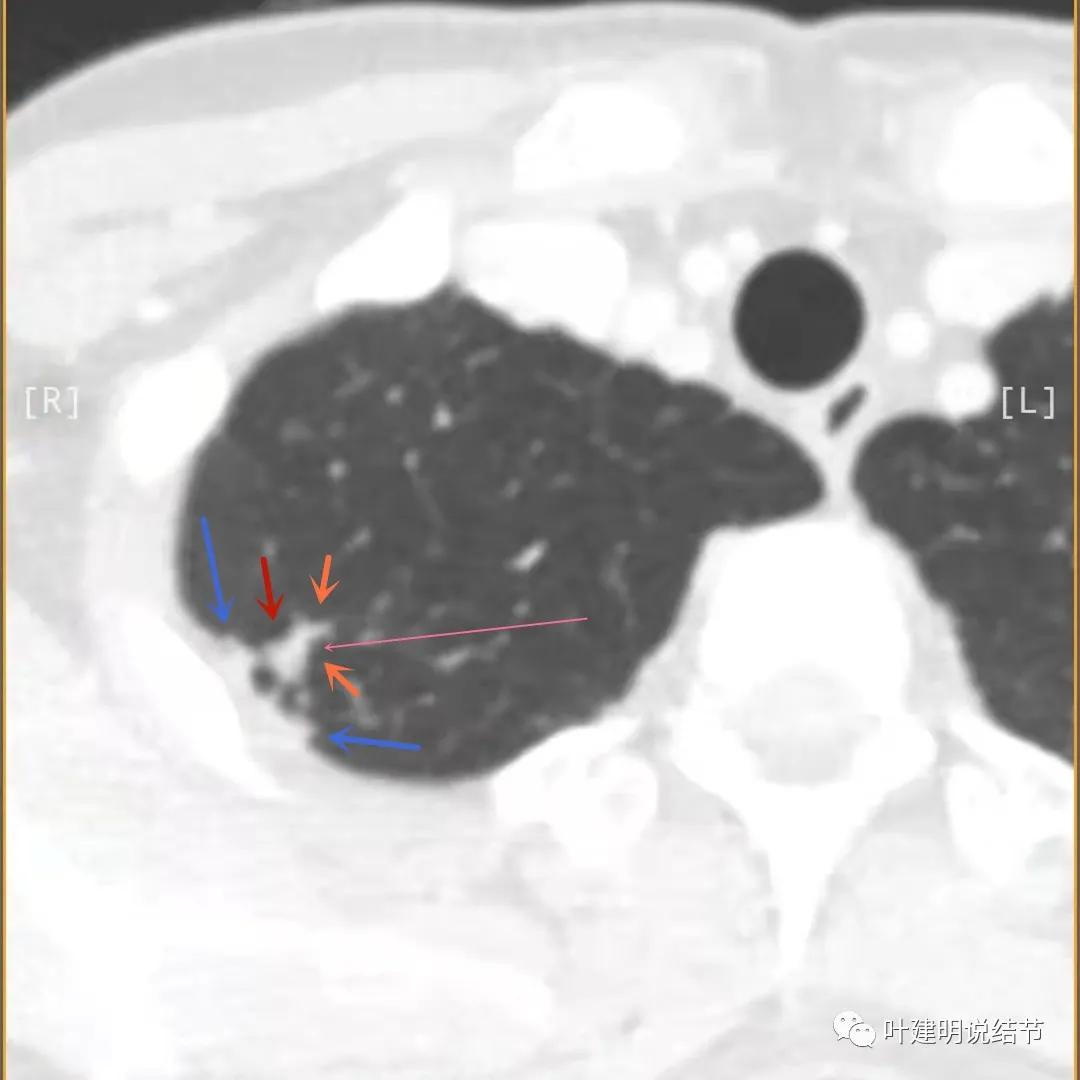

上图与恶性较为符合,空洞性病灶,壁厚薄不均,增厚部分还凹凸不平(细红色箭头所指)

上图磨玻璃部分密度过低,且与正常肺组织界限模糊(砖色箭头),粉色箭头示囊壁密度过高的点状,蓝色箭头示邻近胸膜处的增厚

上图也像恶性,但整个囊壁的密度感觉过高了点,边缘磨玻璃淡、散且模糊,邻近胸膜有增厚

上图病灶的边相对比较光,没有毛刺征,邻近胸膜增厚

上图病灶边缘比较平直,没有膨胀性(桔色箭头),旁边的磨玻璃影淡且界限不清,邻近胸膜增厚。

再看影像印象:病灶较1年前有所进展,部分层面像恶性,囊壁厚薄不均,内面有小突起。但邻近胸膜增厚,旁边的磨玻璃部分散且淡,边界不清,实性部分边相对较光,囊壁有点状过高密度。良性可能性大些,恶性不能除外。